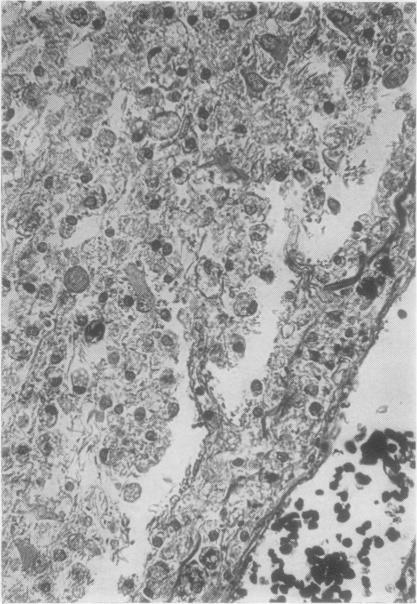

The clinical and pathological findings are described of a fatal case of acute haemorrhagic leucoencephalitis and disseminated encephalomyelitis with acute necrosis of the white matter of the spinal cord. It is suggested that the reaction was a severe immunological response of an allergic nature, probably due to antitetanus serum.